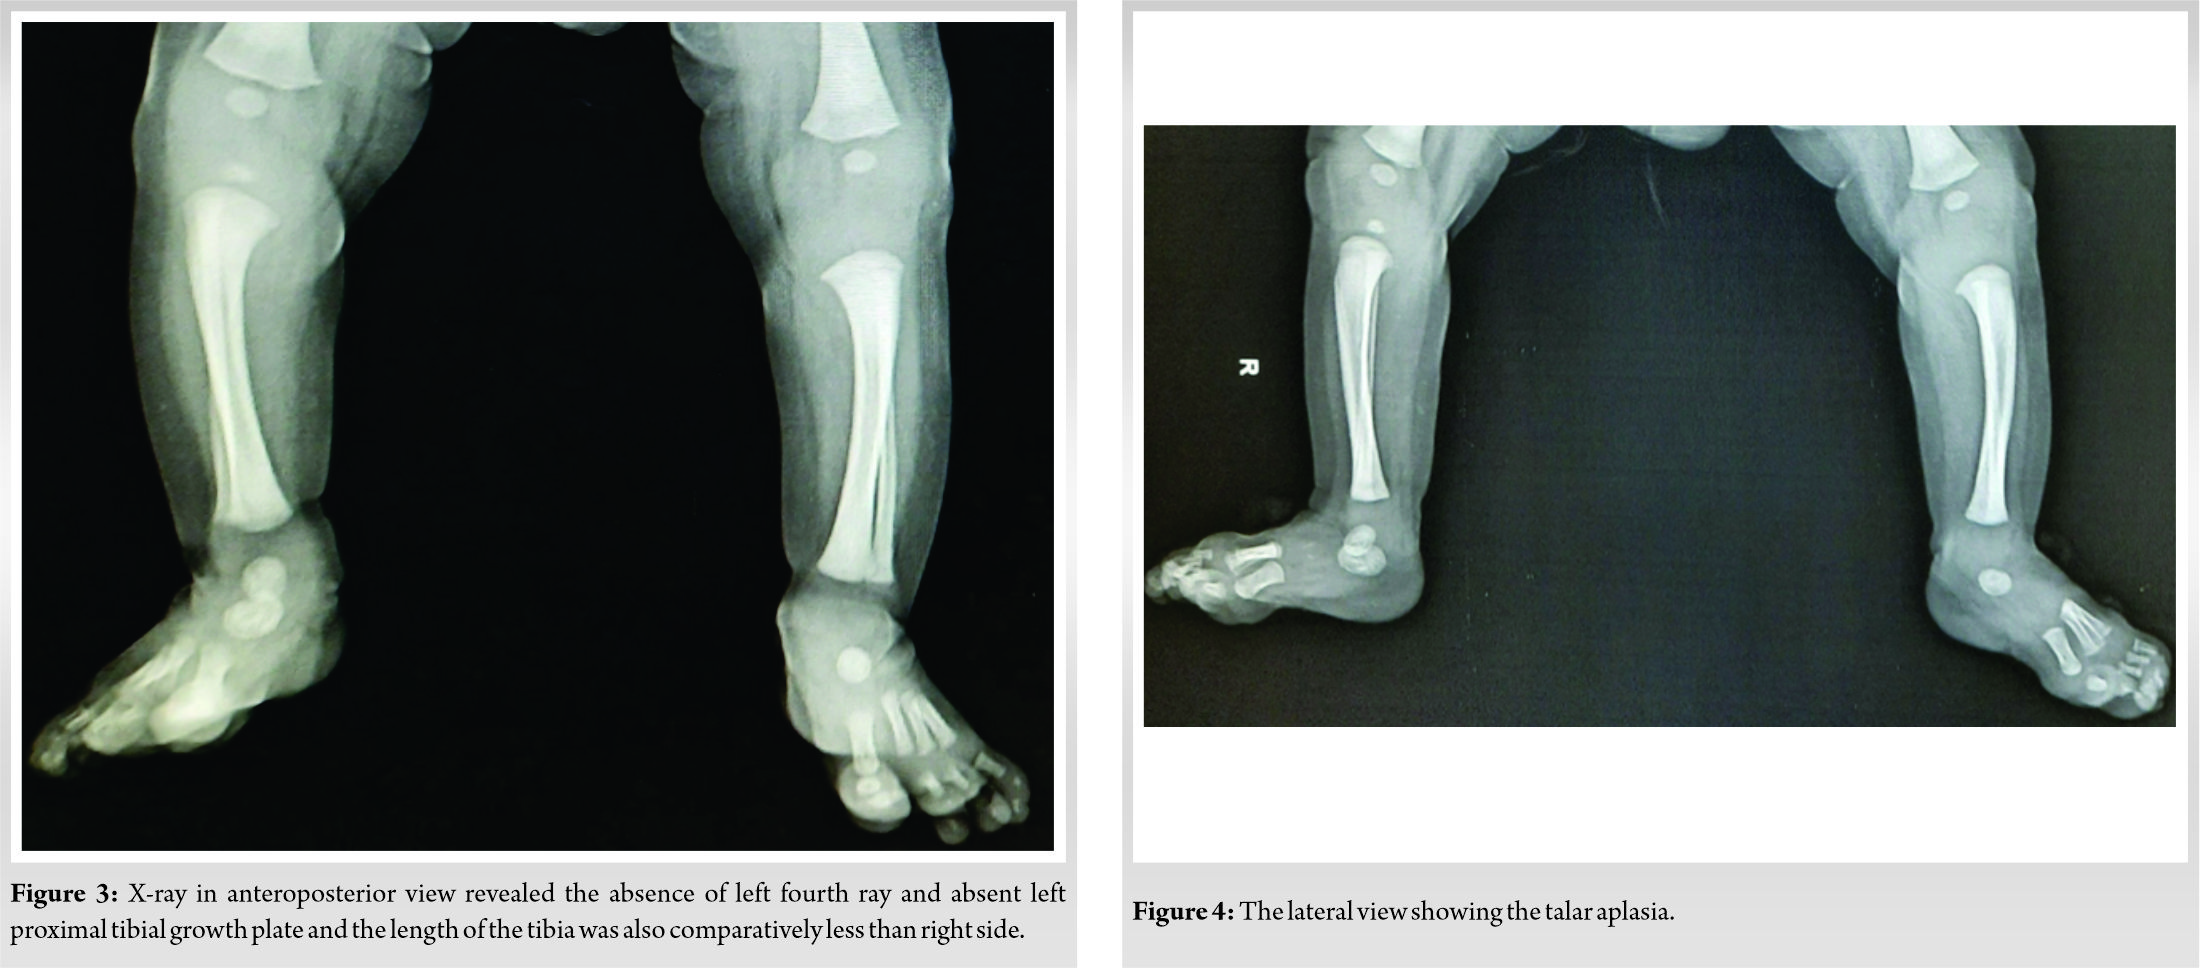

On inspection of the lower limb of the baby, the left leg was short and thin in comparison to the right side (Fig. 1). The left foot appeared shorter due to absent fourth ray and the syndactyly was between 2nd and 3rd toe (Fig. 2). There was no bowing or associated skin dimpling over the limb. On palpation, the ankle joint was normal but the left knee was laxed on a medial and lateral stress test in comparison to the right side. Examination of another side of the limb, upper limb, face, pelvis, and spine were normal. Systemic examination did not reveal any additional findings. The X-ray of the lower limb showed the absence of proximal tibial epiphysis, absent talus, and absence of the fourth ray on the left side. Due to the absent left proximal tibial epiphysis, the tibia, as well as the fibula, was shorter than the normal side (Fig. 3, 4).